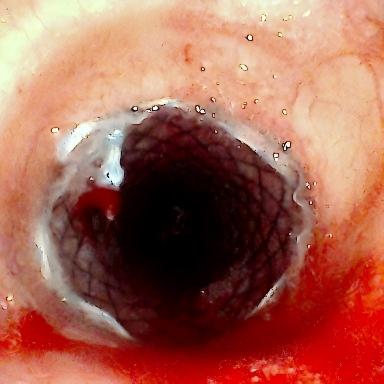

患者为75岁女性,因“反复咳嗽咳痰、气促10余年,加重3月”,于3月3日入住湘雅三医院呼吸与危重症医学科。入院时患者呼吸困难症状严重,CT检查提示气道存在严重狭窄,随时面临窒息风险。经管床医生杨红辉副主任医师评估,患者气管狭窄情况复杂:最狭窄处管腔直径仅剩1-3mm,科室最细的4.0mm支气管镜也无法通过;狭窄位置极低,下缘距隆突仅1.6cm,意味着无法通过气管切开绕过病灶;狭窄处周围组织的CT值高达60-70Hu且无强化,因而直接植入支架存在无法撑开或加重堵塞的风险;同时,患者无法耐受全身麻醉,仅能采用利多卡因进行表面麻醉,操作难度较大。

方案确定后,ICU团队为何智辉、邢伟、邓龙天为患者建立体外生命通道;呼吸介入团队孟婕、杨红辉、刘建明、邹丽君、贺一峻等通过球囊对狭窄部位进行预扩张,随后在距隆突仅1.6cm的低位气道精准植入支架。支架贴合良好,气道顺利开通,全程操作约1.5小时。患者当晚撤离ECMO,次日从ICU转回普通病房。后续肺泡灌洗液检测显示,患者大气道狭窄的原因为气管结核导致的瘢痕性狭窄。